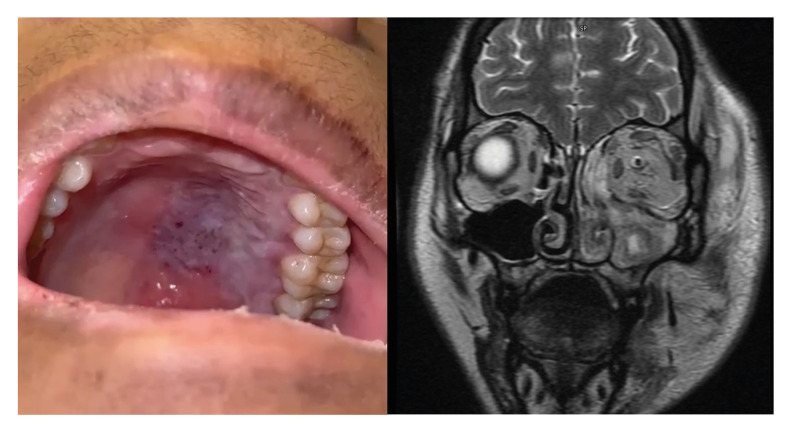

Background:  Craniofacial mucormycosis is a highly lethal infectious disease. This study aims to assess and analyze multiple variables, including clinical, socioeconomic, and biochemical markers, to identify and examine risk factors for mortality associated with this mycotic infection.

Material and methods:  A retrospective analysis was conducted on 38 patients who sought medical attention at the Otolaryngology and Head and Neck Surgery Division of a tertiary-level hospital in Monterrey, Mexico. A broad range of variables was analyzed: clinical features, including the extent of mucormycosis infection; socioeconomic factors such as monthly income, marital status, geographical residence, educational level, and insurance status; as well as biochemical markers, including glucose levels, lactate dehydrogenase (LDH), C-reactive protein (CRP), erythrocyte sedimentation rate (ESR), and immune cell counts, specifically neutrophils (NEU) and lymphocytes (LYM). Statistical analysis was conducted using SPSS v26. Risk factors for mortality were evaluated using Cox regression. Overall survival (OS) was assessed with the Kaplan-Meier method. The Fisher's exact test and the Chi-square test were used for categorical variables. For median comparisons, the Student's t-test and Mann-Whitney U test were applied; with normality assessed using the Shapiro-Wilk test. A p-value <0.05 was considered statistically significant.

Results:  Mucormycosis was associated with higher mortality in men (p=0.032). The disease primarily affected the paranasal sinuses (p=0.021) and was associated with increased mortality when involving the orbit (p=0.035). Additionally, compromised lymphocyte counts (LYM) (p=0.034) and lower educational levels (p=0.009) were associated with higher mortality. Individuals residing in rural areas also exhibited an elevated risk of mortality (p =0.023).

Conclusions:  Prevention strategies should focus on high-risk groups to reduce the mortality rate of craniofacial mucormycosis, particularly targeting men and individuals residing in rural areas. Special emphasis should be placed on those without education or health insurance. Early diagnosis and appropriate management are crucial for improving outcomes.